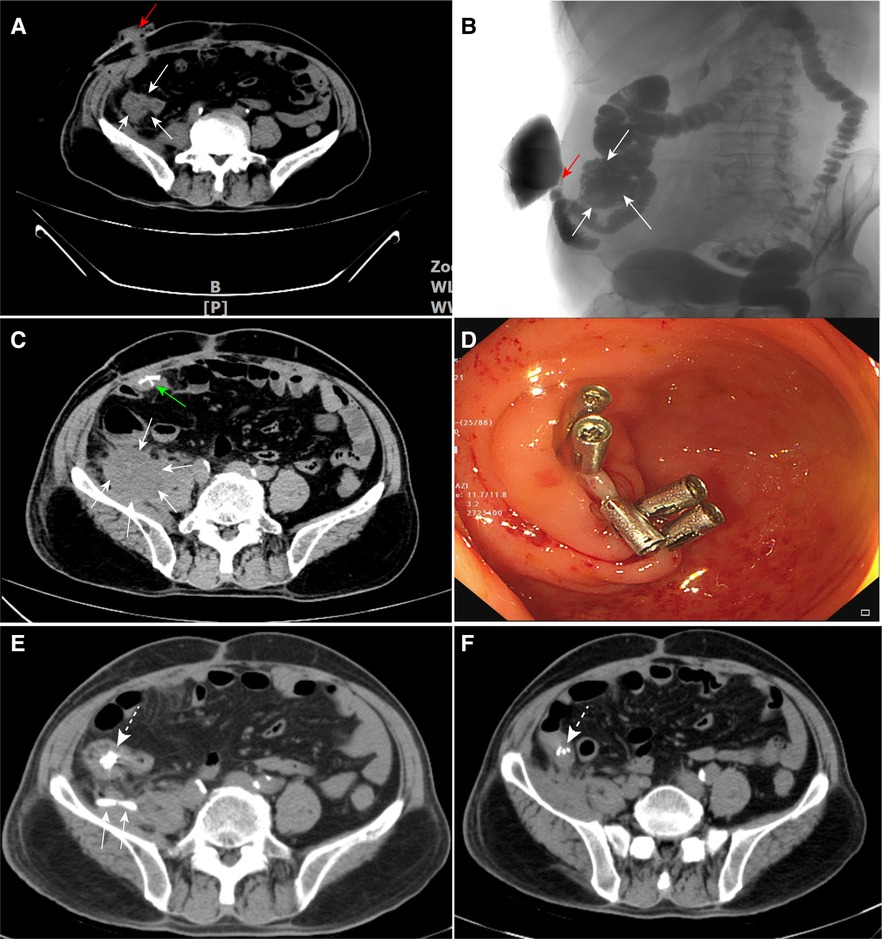

From www.frontiersin.org

Frontiers Colonoscopic titanium clipping to Maddress appendiceal What Is An Inverted Appendiceal Stump The appendix may be inverted in one of the following situations. Stump appendicitis is defined by the recurrent inflammation of the residual appendix after the appendix has been only partially removed. Appendiceal inversion is an uncommon entity that presents a diagnostic dilemma for the gastroenterologist or surgeon. First, the appendix could be inverted surgically, typically after. The goal of this. What Is An Inverted Appendiceal Stump.

Frontiers Colonoscopic titanium clipping to address appendiceal stump What Is An Inverted Appendiceal Stump First, the appendix could be inverted surgically, typically after. Although asymptomatic, ai should be. The appendix may be inverted in one of the following situations. Appendiceal inversion is a rare, but harmless finding that has been described in only a limited number of case reports in the literature. The goal of this case series is to familiarize gastroenterologists and surgeons. What Is An Inverted Appendiceal Stump.